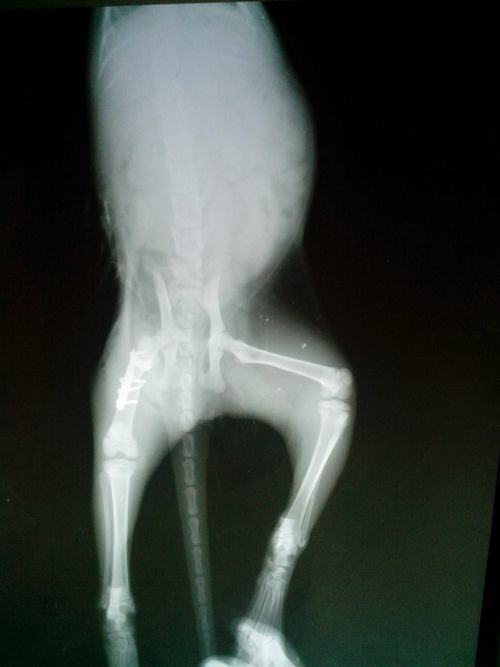

股骨处由于已经近乎断到大转子处,如果采用髓内针则上部没有足够的着力点,固定的效果不理想,所以手术采用螺钉固定斜骨折,L型接骨板桥接断端。

手术中所使用的L型接骨板

用骨螺钉和接骨板固定后的X光图